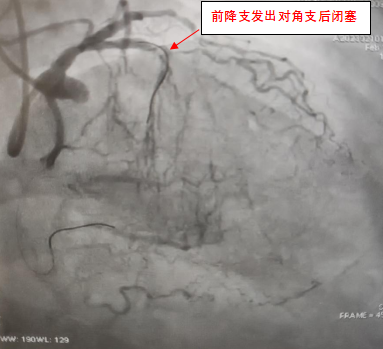

2月10日,洪浪团队对外院冠脉造影评估,患者前降支中段CTO,无残端,并且第一对角支近段也存在重度狭窄,属于CTO+分叉病变,手术有一定的难度和风险。虽然经验丰富,但团队的每位医生都不敢掉以轻心。洪浪院长与主管医生常智堂、曾洪、王晶、黄媛、刘子铭等进行了充分的术前讨论,准备了多套手术方案,为手术做好充分的准备。